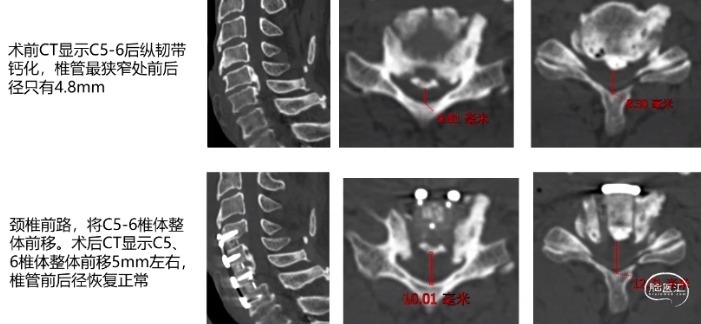

整体迁移融合技术ACAF